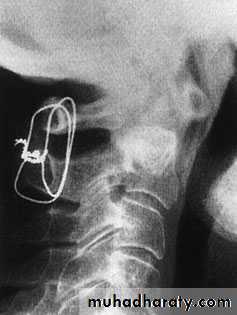

Cervical Spine X-RayLateral radiograph

A/P radiographThoracic Anatomy